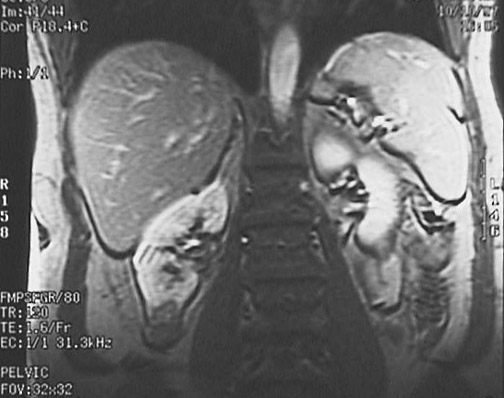

This coronal MRI scan of the abdomen demonstrates a small renal cell carcinoma of the lower pole on the right.